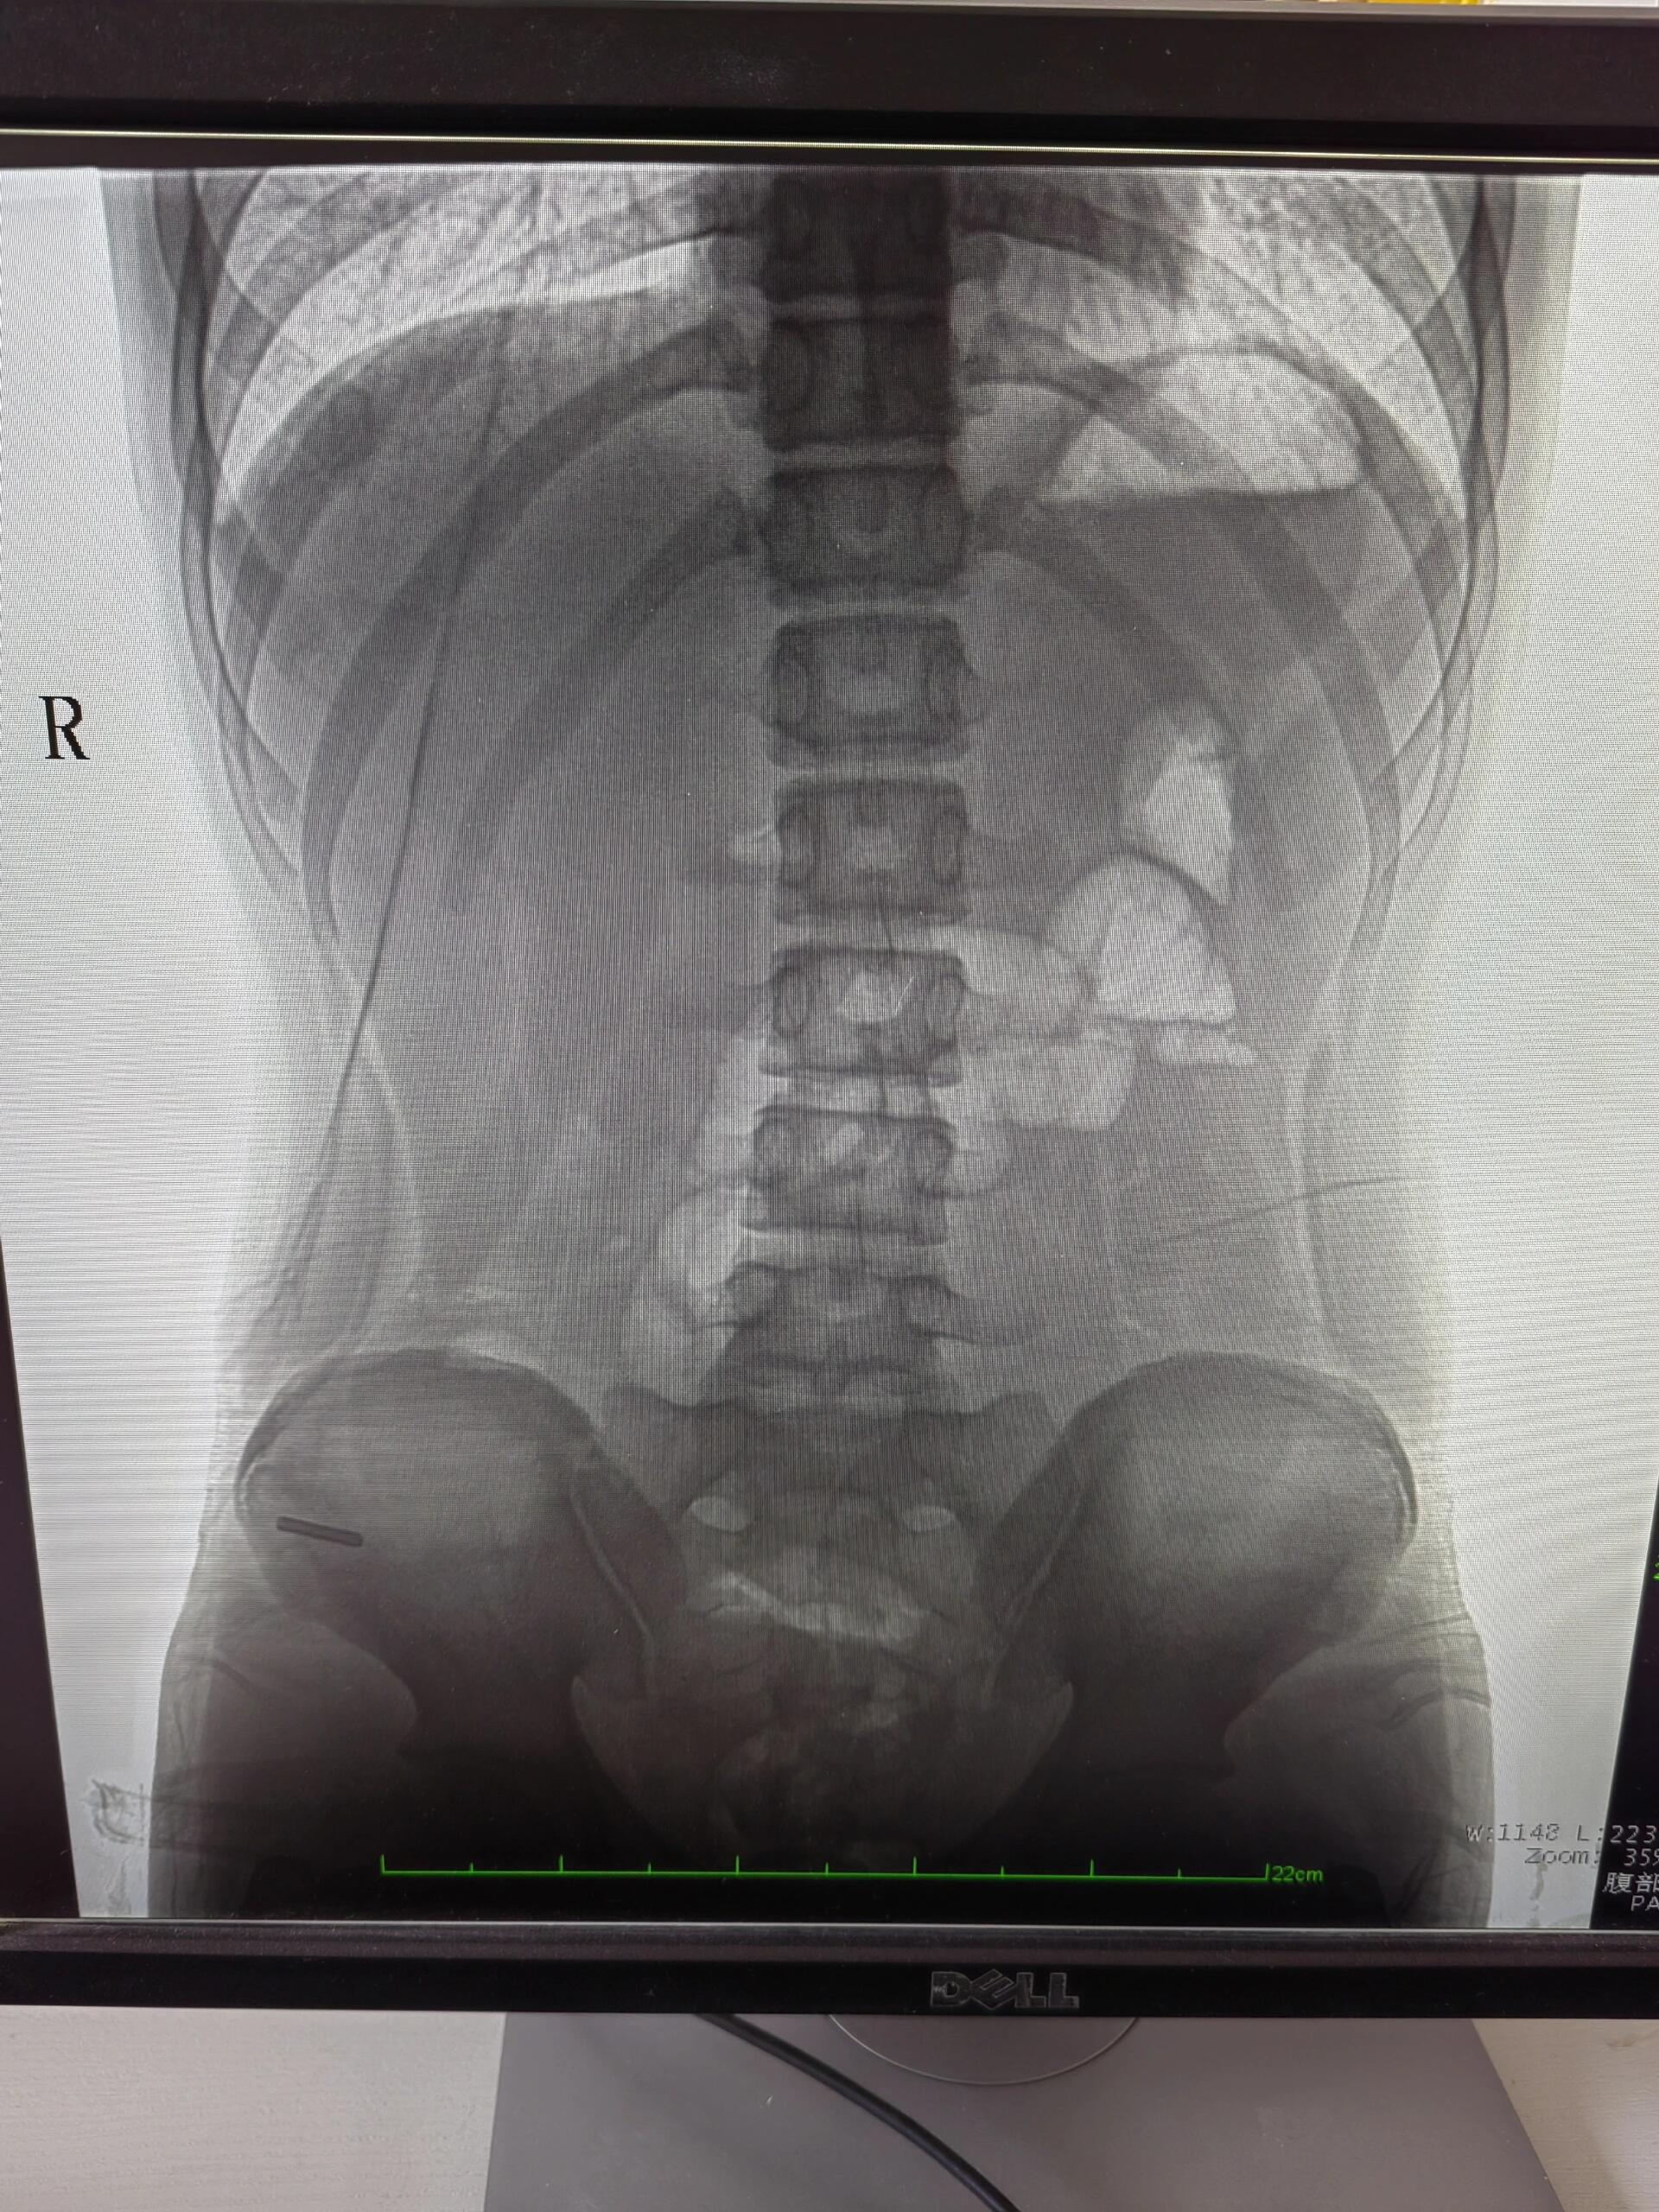

肠梗阻的典型症状以消化系统功能紊乱为核心,主要表现为以下方面1 腹痛与腹胀患者常出现阵发性或持续性腹部绞痛,疼痛位置多集中于脐周或梗阻部位,伴随腹部胀满感腹胀程度与梗阻部位及类型相关,高位梗阻如小肠腹胀可能较轻,低位梗阻如结肠腹胀更显著2 停止排便排气肠道内容物通过受阻。

肠梗阻的四大症状为腹痛呕吐腹胀停止排气排便,具体表现如下1 腹痛腹痛是肠梗阻最突出的症状梗阻部位以上的肠道因强烈蠕动引发阵发性绞痛,疼痛多集中于脐周或下腹部,发作时可能伴有肠鸣音亢进肠蠕动增强的声音不完全性肠梗阻的腹痛多为间歇性,而完全性肠梗阻的腹痛则呈持续性且更剧烈。